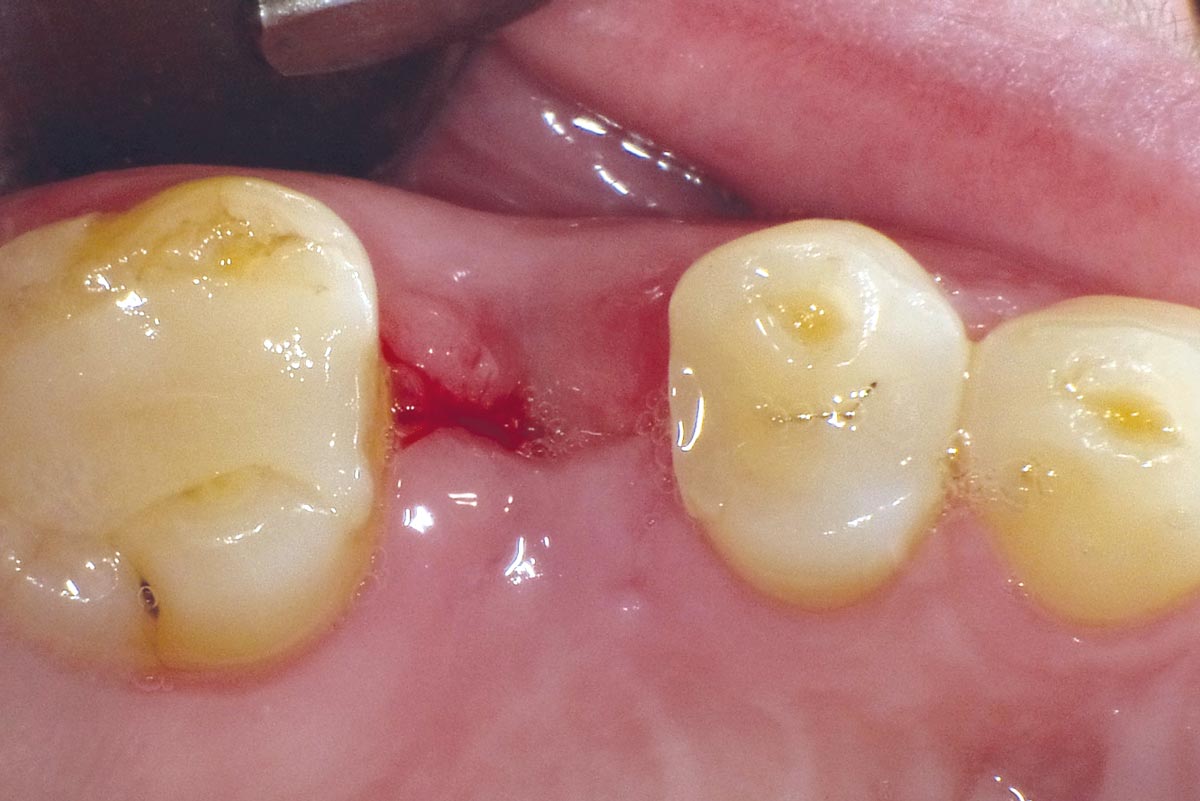

1/10 - Intact socket following atraumatic tooth extractionSocket seal with mucoderm® punch - Dr. G. Muhle